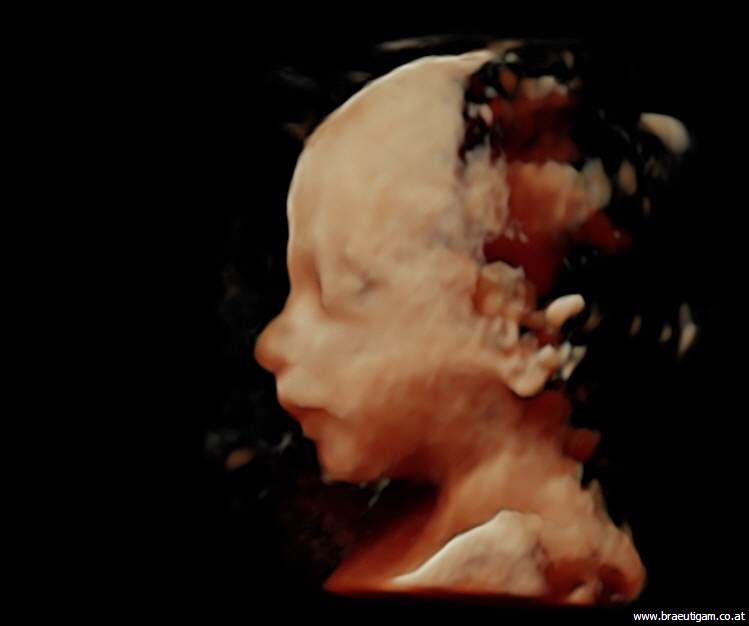

Aufgrund einer hohen technischen Ausstattung in meiner Ordination ist es mir möglich ein dreidimensionales Bild von Ihrem Kind anzufertigen. Die Kindsbewegungen können „live“ am Bildschirm mitverfolgt werden (4D).

Dieses ermöglicht einerseits die bessere Diagnostik einiger Fehlbildungen wie etwa der Lippen-Kiefer-Gaumenspalte, andererseits kann so das erste "Foto" von Ihrem noch ungeborenen Kind gemacht werden, was die Mutter-Kind-Beziehung zusätzlich fördert und sicherlich eine nette Erinnerung an diese außergewöhnliche Zeit ist.

Ein 4-D-Bild |